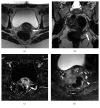

Magnetic resonance neurography is a high-resolution imaging technique that allows evaluating different neurological pathologies in correlation to clinical and the electrophysiological data. The aim of this article is to present a review on the anatomy of the lumbosacral plexus nerves, along with imaging protocols, interpretation pitfalls, and most common pathologies that should be recognized by the radiologist: traumatic, iatrogenic, entrapment, tumoral, infectious, and inflammatory conditions. An extensive series of clinical and imaging cases is presented to illustrate key-points throughout the article.